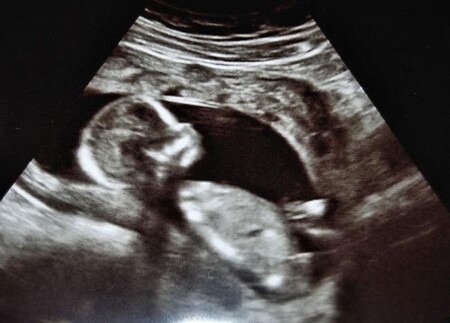

ecografía de bebé

Al comenzar el segundo trimestre de embarazo el bebé ya tiene un aspecto muy similar a un recién nacido, pero mucho más pequeño.

Tanto es así, que entre la semana 14 y 16 su talla estará entre los 10-11 cm desde la coronilla hasta el final de la espalda, cabiendo en la palma de una mano. Entre las semanas 16 y 20 el bebé crecerá hasta alcanzar los 350 gramos de peso y los 16 cm de longitud, y al término del trimestre su longitud llegará a los 36 centímetros y su peso a los 1.100 gramos.

Su cuerpo crece de manera proporcionada, y la cabeza ya no representa el doble de su cuerpo como en las primeras semanas.

En este segundo trimestre, los órganos del bebé están en un estado muy avanzado de su desarrollo, aunque algunos, como los pulmones, deben continuar madurando hasta el último momento. Su esqueleto también comienza a fortalecerse y esto hará que sus movimiento dentro del útero empiecen a hacerse notables entre la semana 16 y 20, dependiendo de si es el primer embarazo o no. Sentir las primeras pataditas de tu bebé es realmente maravilloso y una experiencia que jamás olvidarás.